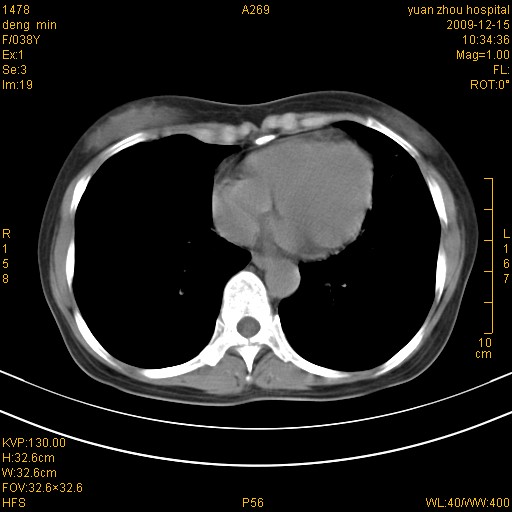

标题: CT23919:F38Y 咳嗽月余 [打印本页]

标题: CT23919:F38Y 咳嗽月余

右肺中下叶、左肺上叶舌段及左肺下叶支气管扩张合并感染。